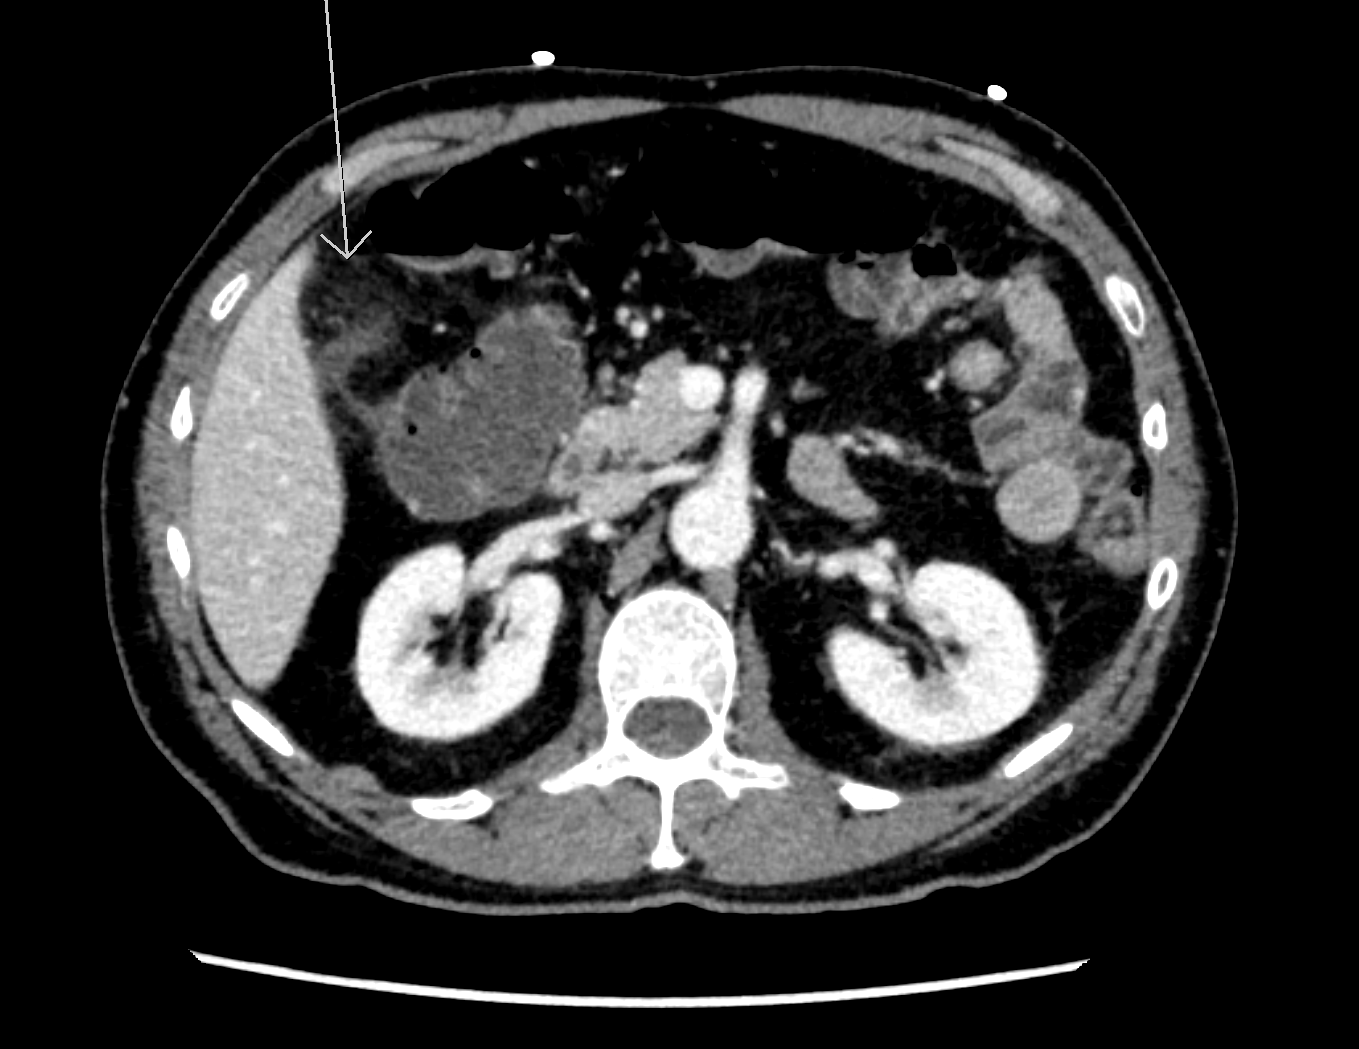

The patient was referred to ultrasound with suspicion of acute cholecystitis as a possible primary diagnosis and acute appendicitis as a secondary possibility. An ultrasound examination of the abdomen was performed using a GE Logiq E9 system with a curved array transducer with a frequency of 1-6 MHz (GE, Chalfont St. Giles). The examination revealed sludge and a stone of approximately 1 cm in the gallbladder. There was no dilatation of the intra- or extrahepatic bile ducts and the gallbladder wall was without thickening (below 3 mm). The other abdominal organs were normal. The appendix could not be seen. Due to the discrepancy between the clinical history, the imaging findings and the planned cardiac surgery the day after, a CT examination was performed to exclude appendicitis. CT showed pericholecystic fat stranding, confirming the diagnosis of cholecystitis. The appendix was located behind the cecum and appeared normal. No other pathology was reported.